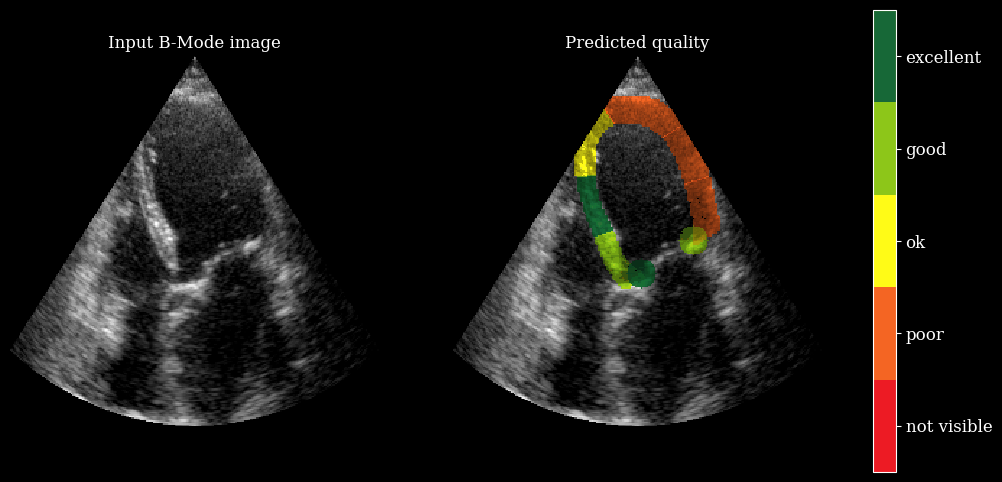

Now we will run the segmentation model to get the LV and myocardium masks, and then feed those to the image quality model to get regional quality scores.

[6]:

# onnx model needs [batch, channels, height, width]

batch_np = ops.convert_to_numpy(batch)

onnx_input = np.transpose(batch_np, (0, 3, 1, 2))

# Run the image quality model

scores = quality_model.call(onnx_input)

scores = np.array(scores)

# Run the segmentation model (LV + myocardium)

outputs_seg = seg_model.call(onnx_input)

outputs_seg = np.array(outputs_seg)

masks = np.argmax(outputs_seg, axis=1).astype(np.uint8)

fig, ax = plt.subplots(1, 1, figsize=(5, 5))

ax.imshow(batch_np[0], cmap="gray")

plot_shape_from_mask(ax, masks[0] == 1, color="red", alpha=0.3)  # LV

plot_shape_from_mask(ax, masks[0] == 2, color="blue", alpha=0.3)  # Myocardium

plt.axis("off")

plt.show()

region_labels = [

"basal_left",

"mid_left",

"apical_left",

"apical_right",

"mid_right",

"basal_right",

"annulus_left",

"annulus_right",

]

print("Predicted regional image quality scores:")

for label, score in zip(region_labels, scores[0]):

print(f"  {label}: {score:.2f}")

../../_images/notebooks_metrics_myocardial_quality_example_10_0.png

Predicted regional image quality scores:

basal_left: 4.59

mid_left: 5.21

apical_left: 3.60

apical_right: 2.37

mid_right: 2.64

basal_right: 2.99

annulus_left: 6.01

annulus_right: 4.85

We need the arqee package for a complete visualization. The colored overlay shows the predicted regional image quality for each myocardial region.